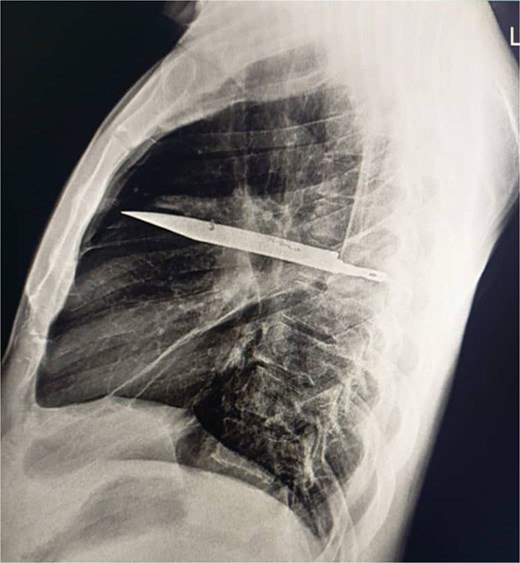

В Танзании 44-летний мужчина восемь лет прожил с ножом в груди, не обращаясь за медицинской помощью — JSCR (Журнал хирургических отчетов)

Мужчина обратился к медикам с жалобами на гнойные выделения из правой грудной пазухи, при этом других симптомов вроде сильных болей или повышенной температуры он не испытывал, и его медицинские показатели были в норме. Лезвие ножа в его груди нашли с помощью рентгена и компьютерной томографии.

Выяснилось, что восемь лет назад пациент пострадал в драке, получив множество ножевых ранений, однако тогда ему оказали лишь первичную медицинскую помощь. Операция по удалению ножа шла несколько часов и завершилась успешно, мужчина восстановился без осложнений.